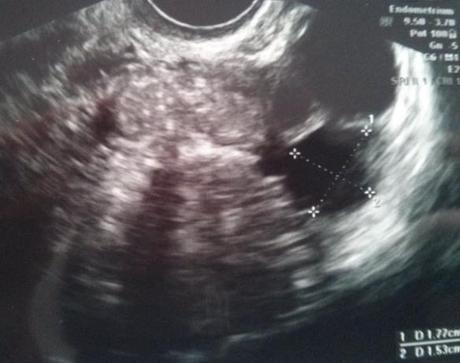

En la siguiente foto tenéis la ecografía. En la primera foto se mide el residual, y en la segunda el mediano. En la segunda foto se ve mejor ese otro “foliculín” entre los dos más grandes.

Le tuve que recordar la existencia del folículo residual, tomó medidas y comprobó que efectivamente se trataba del mismo. En ese mismo ovario, el derecho, había otros dos folículos, de los cuales, uno era mediano y otro pequeño.